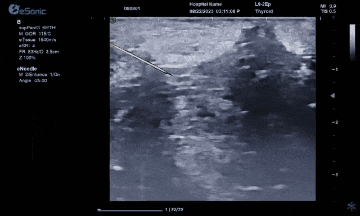

而准台式RTE弹性成像在超声介入应用中又是一大助力。操作简单、高实时性高重复性、通过颜色可直观评评估组织软硬程度。也有助于非肿块区域硬度异常的发现和评估。在穿刺中可引导穿刺到硬度较大的区域,提高穿刺阳性的成功率。

智能介入解决方案、无磁导航,可以在比较复杂的环境中,如ICU、其它床旁等场景下应用时,不会受周围机器的影响。另外,除了常规的穿刺针智能增强,支持针体增强程度调节外,智能穿刺针彩色Map技术又是3377体育医疗(ESI)准台式超声的首创技术。在超声引导穿刺消融的过程中,能够增强穿刺针与组织的对比度,清晰显示针尖与针体。